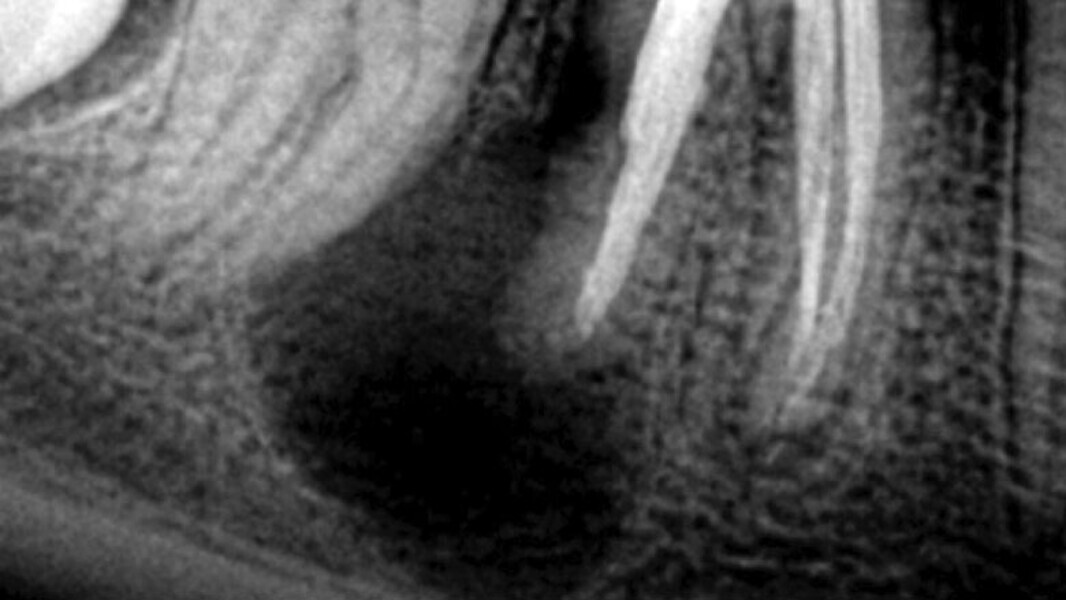

Figura 2. Lesión periapical en el diente 46 (primer molar inferior derecho) de gran tamaño. Iniciando una reabsorción radicular externa en la raíz distal.